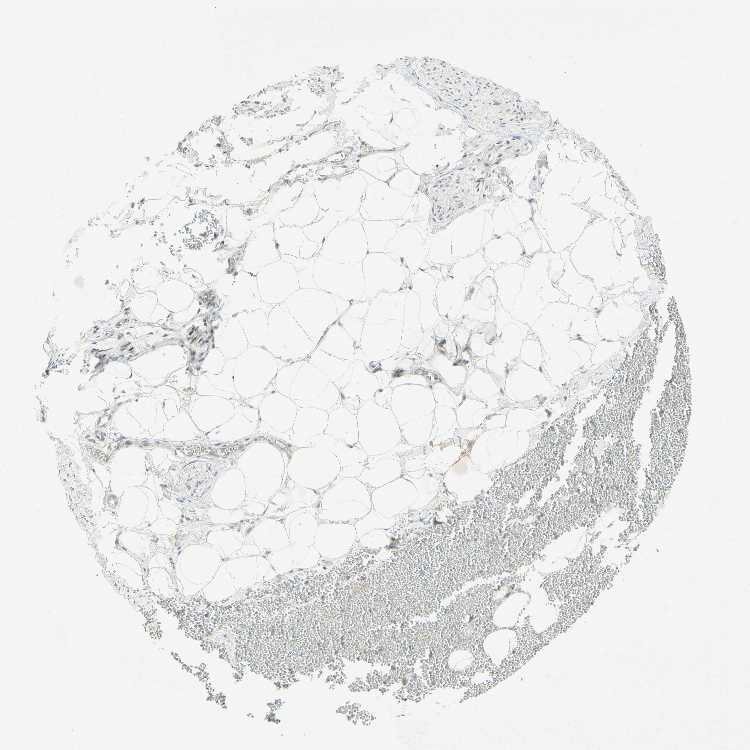

Female, age 80

Adipose tissue sample 86

nTPM: 39.5

Cell types%

Adipocytes:

95

Other cell types:

5